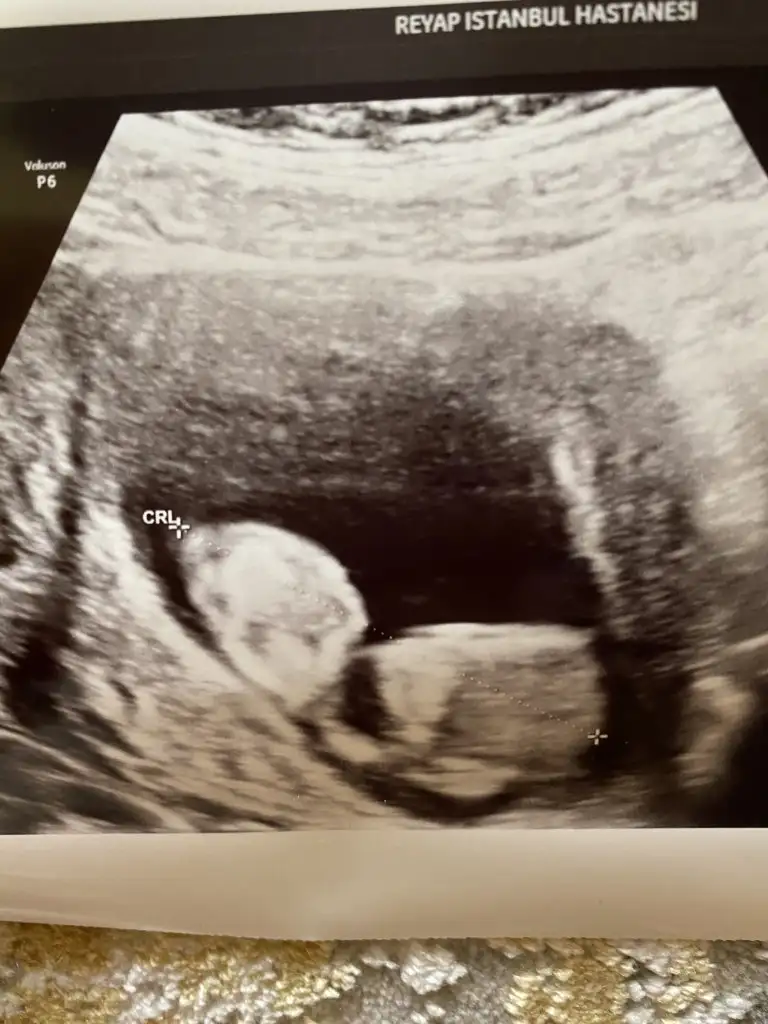

Cnm arkadaşımda tahminde buluna bilirmisin? (vaginal bakilmis) 13. Haftalik

Bu 13. Haftalik vajinal.